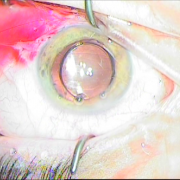

ιριδικής στήριξης

Sun Set Syndrome

πίσω από την ίριδα

φακού